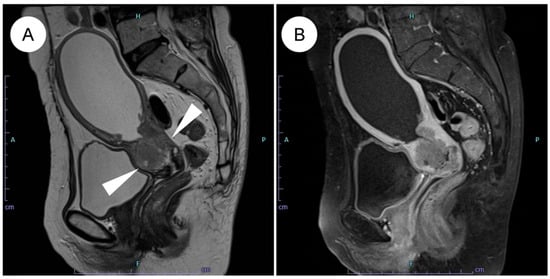

Endocervical adenocarcinoma is now classified within an etiologic framework based on the presence or absence of high-risk human papillomavirus (HPV) infection. Gastric-type endocervical adenocarcinoma (GAS) is the prototypical HPV-independent subtype, accounting for up to 25% of endocervical adenocarcinomas and showing a particularly high [...] Read more.

Endocervical adenocarcinoma is now classified within an etiologic framework based on the presence or absence of high-risk human papillomavirus (HPV) infection. Gastric-type endocervical adenocarcinoma (GAS) is the prototypical HPV-independent subtype, accounting for up to 25% of endocervical adenocarcinomas and showing a particularly high frequency in East Asia. GAS is typically diagnosed at a more advanced stage than usual-type HPV-associated endocervical adenocarcinoma (UEA); exhibits deep stromal and parametrial invasion, lymphovascular space invasion, and a strong propensity for ovarian and peritoneal metastasis; and is associated with markedly worse survival, even in stage I disease. Radiological evaluation is challenging because of diffuse infiltrative growth, prominent mucin production, and frequent underestimation of extra-cervical spread. Histologically, GAS shows gastric-type (pyloric) differentiation, ranging from minimal deviation adenocarcinoma to poorly differentiated forms, and often overlaps with precursor lesions such as atypical lobular endocervical glandular hyperplasia and gastric-type adenocarcinoma in situ. Immunophenotypically, GAS is typically p16-negative, ER/PR-negative, and frequently exhibits mutant-type p53 and expression of gastric markers including MUC6, HIK1083, and claudin 18.2. Recent next-generation sequencing and multi-omics studies have revealed recurrent alterations in TP53, CDKN2A, STK11, KRAS, ARID1A, KMT2D, and homologous recombination-related genes, together with the activation of PI3K/AKT, WNT/β-catenin, TGF-β, and EMT pathways and characteristic metabolic reprogramming. GAS is highly resistant to conventional chemotherapy and radiotherapy, and its current management follows guidelines for squamous and usual-type adenocarcinoma. Emerging data support precision-medicine approaches targeting HER2/HER3, PD-1/PD-L1, and claudin 18.2, and suggest a role for PARP inhibition and other genotype-directed therapies in selected subsets. Given its aggressive biology and rising relative incidence in the HPV-vaccination era, GAS represents a critical unmet need in gynecologic oncology. Future progress hinges on developing reliable diagnostic biomarkers, refining imaging protocols, and validating targeted therapies through international clinical trials. Full article

Show Figures

Figure 1